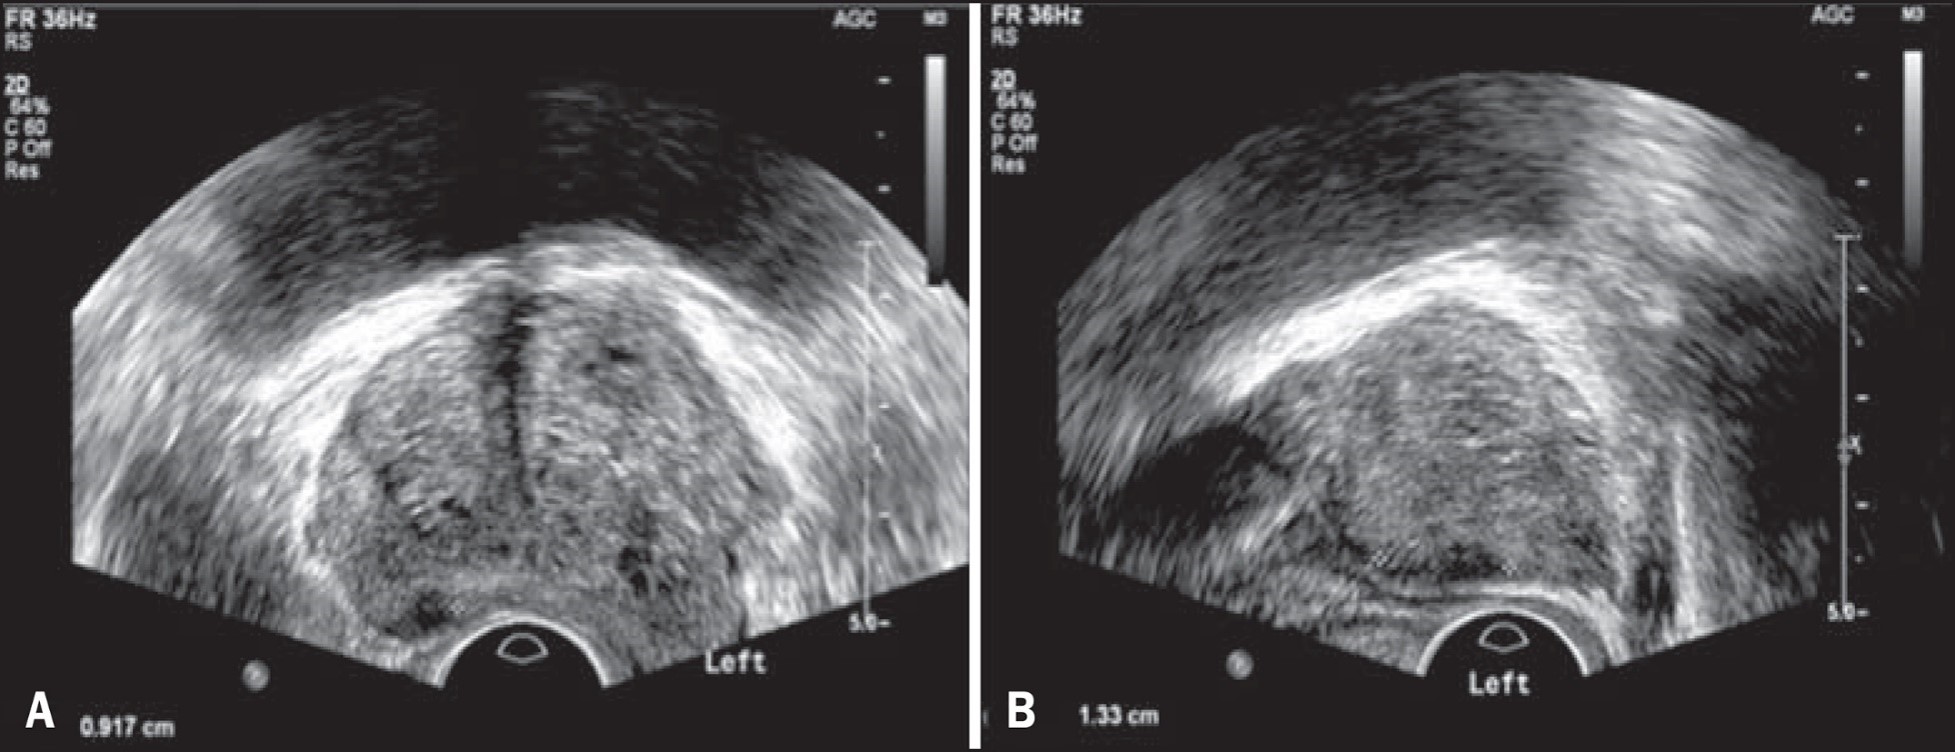

PROSTAT ULTRASONOGRAFİSİ (MAKATTAN/TRANS REKTAL)

Transrektal ultrasonografi denen değerlendirmede, ultrasonografi kalın barsağın son kısmından yapılmaktadır. Parmak kalınlığındaki ultrason probu, parmakla prostat muayenesinde olduğu gibi anüsten kalın barsağa sokulur. Buradan prostat çok ince detaylarına kadar görüntülenebilir. Karından yapılan ultrasonografiye göre prostatın hacmi ve iç yapısı hakkında daha kesin değerlendirmeler yapılabilir.